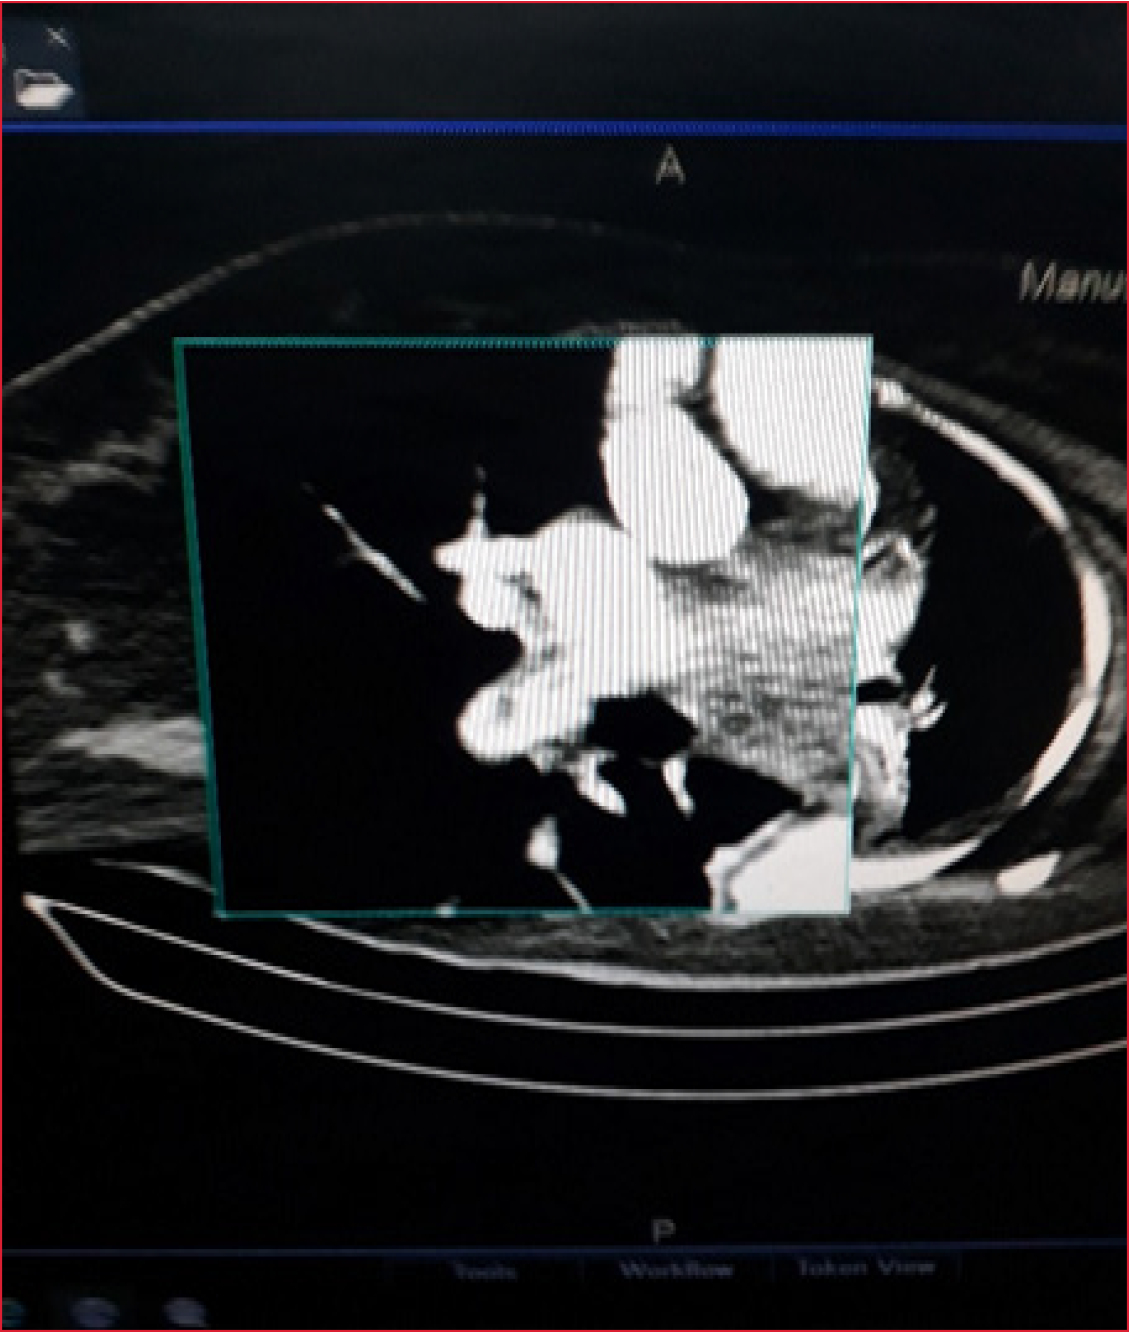

Presentación de caso: paciente de 58 años, femenina, historia de HTA y DM tipo 2 admitida en el hospital Victoria de Seychelles por emergencia hipertensiva e ictus diagnosticandosele por TAC hemorragia intracerebral talamica izquierda con sangrado intraventricular y edema cerebral ademas de neumonia por broncoaspiracion requiriendo soporte ventilatorio. Presento complicaciones: distress respiratorio, barotrauma, neumonia asociada a la ventilación mecánica, bacteremia asociada a catéter venoso central, y enfermedad tromboembolica: trombosis venosa profunda femoral derecha y tromboembolismo pulmonar. A pesar de su evolucion torpida es egresada viva.